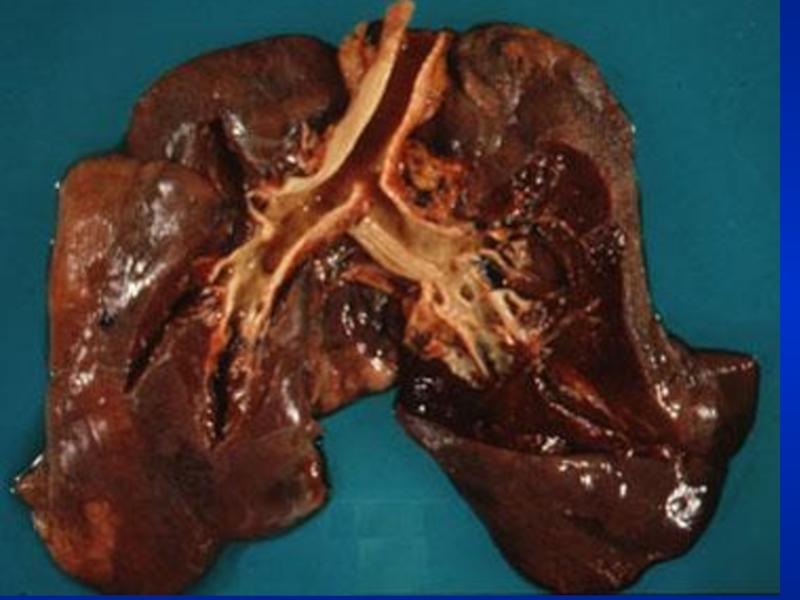

Consolidation

In consolidation, the bronchial breathing

is low pitched and sticky and is termed tubular type of bronchial breathing.

In cavitary disease, it is high pitched and hollow and is called cavernous breathing. You can simulate this sound by blowing over an empty coke bottle.

BronchialBronchial breathing anywhere other than over the trachea, right clavicle or right inter-scapular space is abnormal.In consolidation,